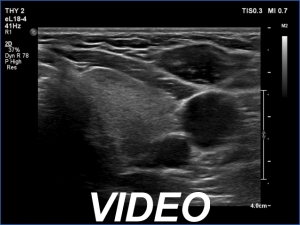

Ultrasonography. The thyroid was echonormal and presented several minimally-moderately hypoechoic areas. One of them, which was located in the central part of the right lobe was deeply hypoechoic and corresponded to pathological nodule. The other lesions seemed to be not true nodules but more active foci of thyroiditis.